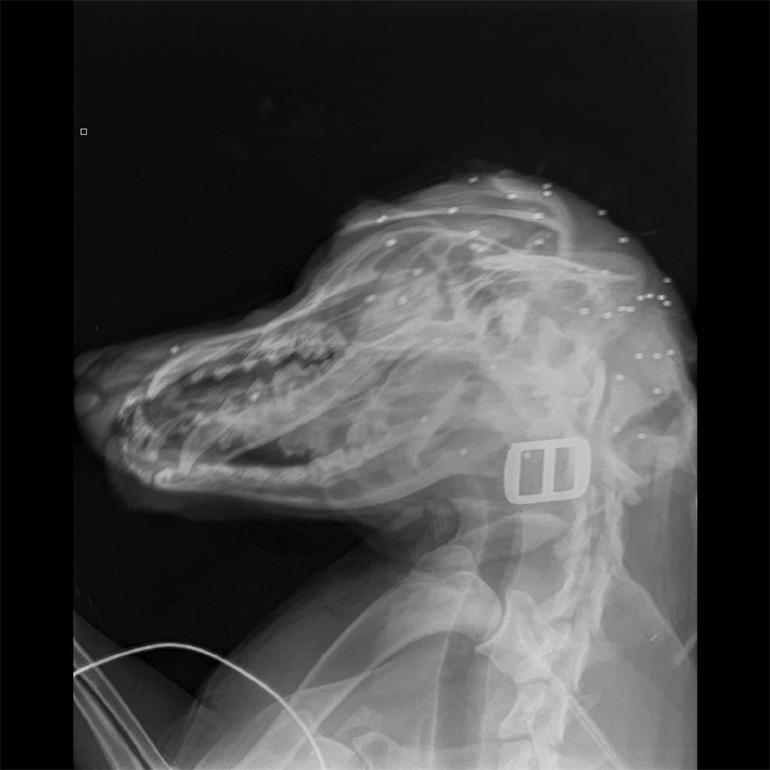

Χάρη στην άμεση κινητοποίηση της οικογένειας, ο σκύλος, που δέχτηκε τριάντα σκάγια στο κεφάλι, θα επιζήσει, ενώ σε βάρος του άνδρα που πυροβόλησε το άτυχο ζώο υπεβλήθη μήνυση.